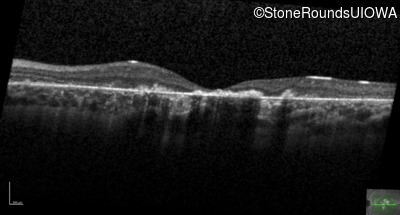

Optical Coherence Tomography - Right - 10/160

Exemplar / OCT Stack

OCT Stack